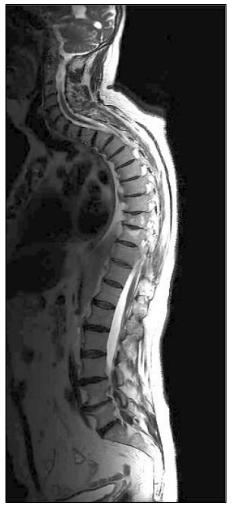

Paciente J.A.P., 68 anos de idade do sexo masculino, lúcido, orientado e com lombalgia crônica há 10 anos (SIC). Foi internado com lombociatalgia (irradiação para MIE). Refere que essa crise iniciou no dia anterior após ter escorregado num piso molhado, mas não houve queda. De acordo com o exame apresentado e com as seguintes informações: paciente diagnosticado com espondilite anquilosante, múltiplas artroses, bem como com protrusões discais e espondilolistese grau I entre L4/L5, assinale o tratamento fisioterapêutico mais adequado para a lombociatalgia.